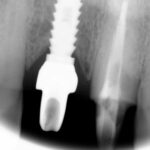

Este paciente llegó al consultorio con reabsorción dentinaria (pérdida de la estructura del diente). Por ello se le extrajo el diente, se le colocó un implante y se restauraron las piezas con coronas de cerámica pura.